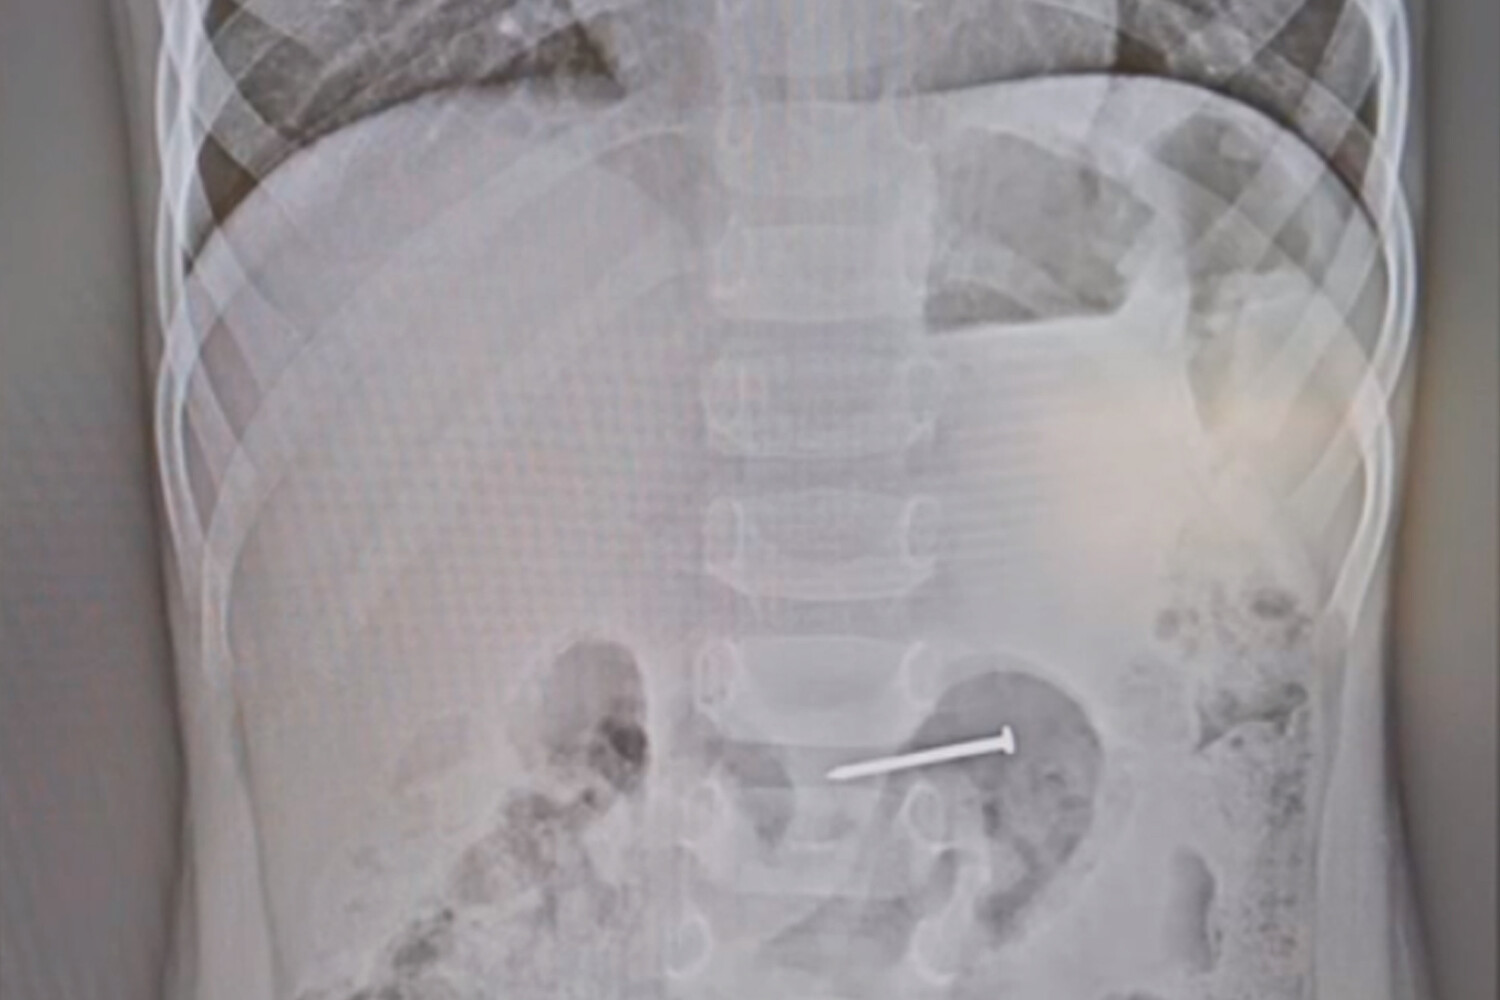

Врачи провели мальчику рентгенографию, которая показала, что в ЖКТ действительно находится инородное тело, а именно гвоздь длиной 2,5 см. По словам медиков, ребенку повезло, что гвоздь удачно расположился в двенадцатиперстной кишке — шляпкой вверх, он ничего не проткнул и не повредил. Мальчику сразу же провели операцию. С помощью эндоскопа врачи за полчаса извлекли инородный предмет. Сутки пациент находился под наблюдением медиков, после чего ему провели контрольное обследование и отпустили домой.